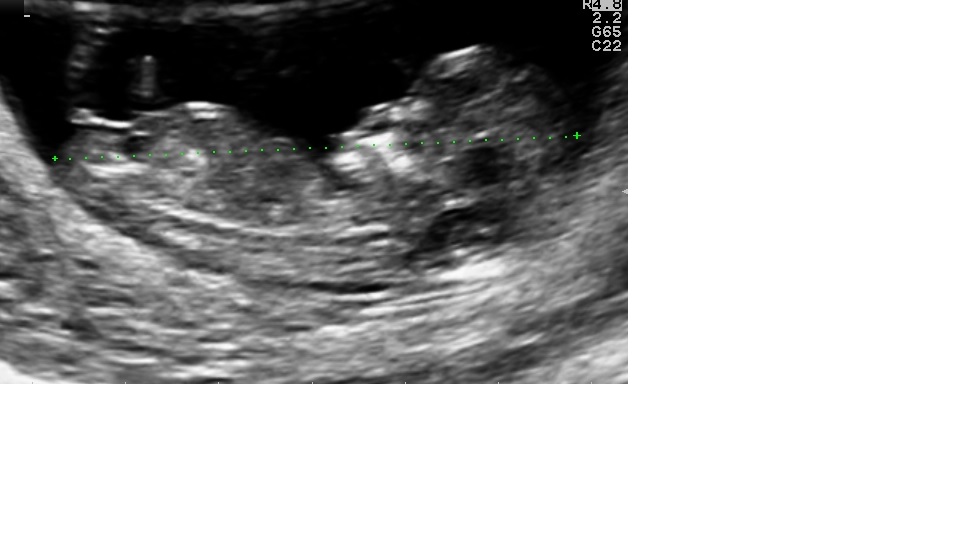

So Curious...what do you think...boy or girl ;-)